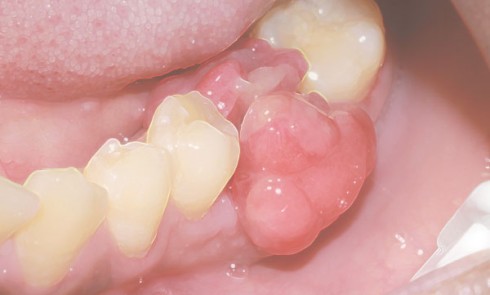

Article réservé à nos abonnés Et si ce n’était pas un lichen ?

Cas 1     Motif de la consultation. Patient de 51 ans venu consulter pour des douleurs jugales gauches. Histoire...